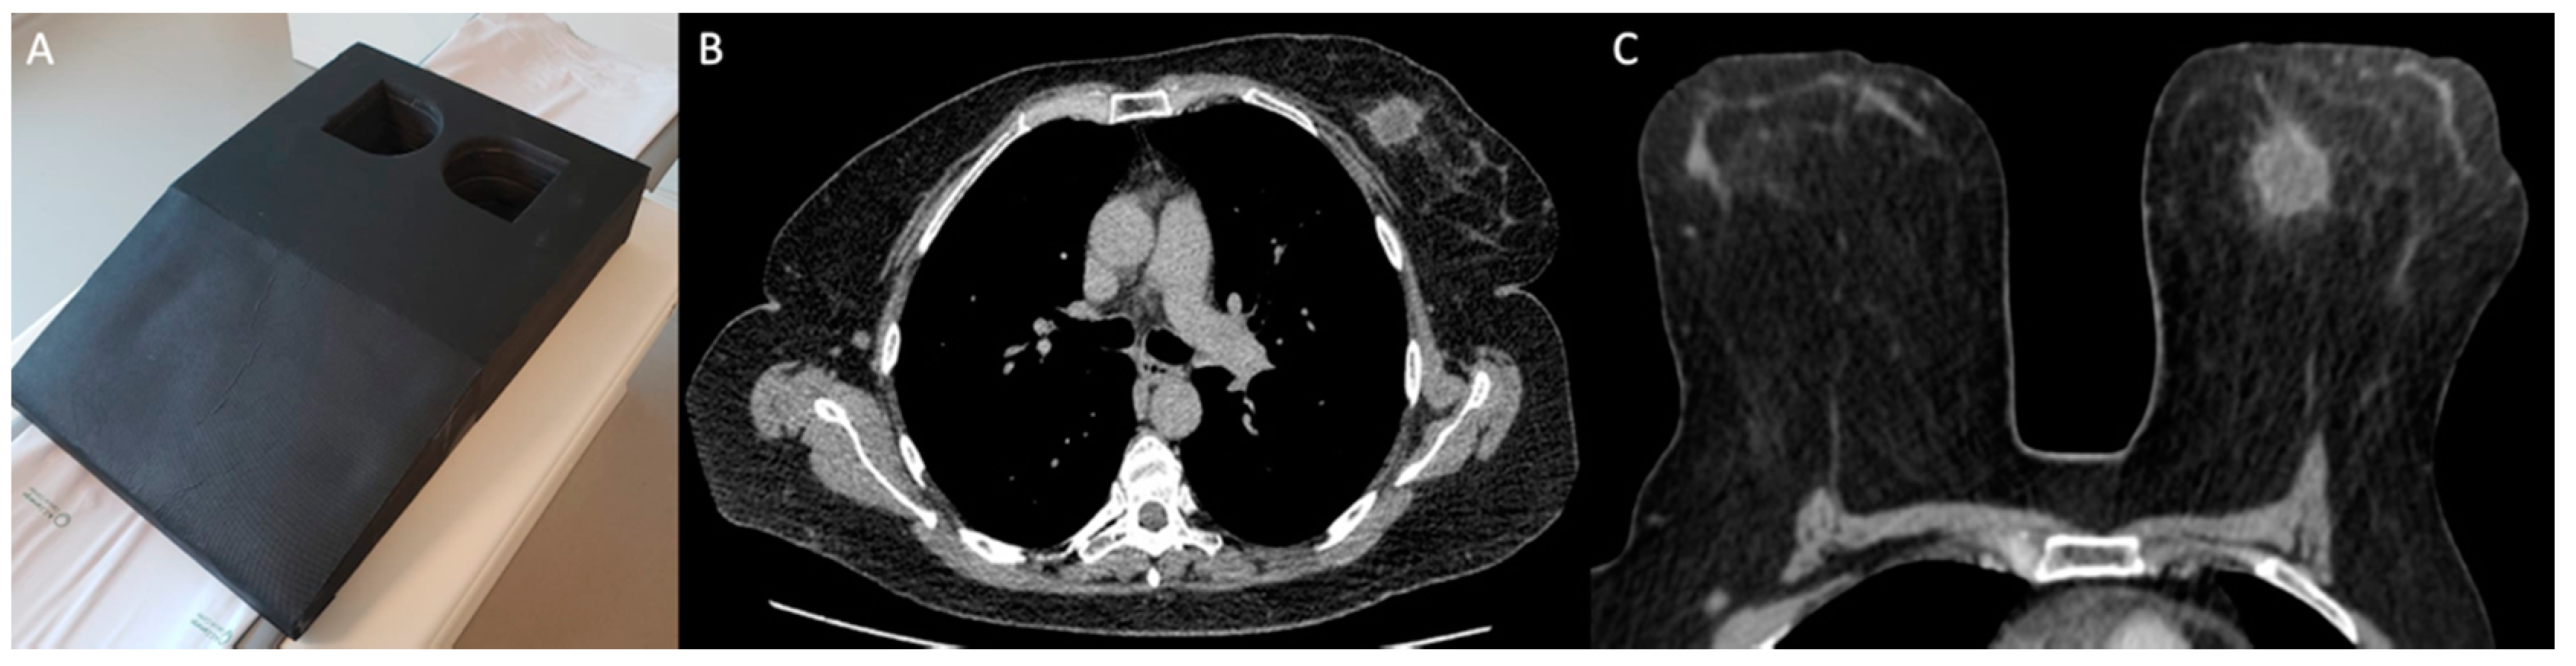

2.3. Imaging Acquisition